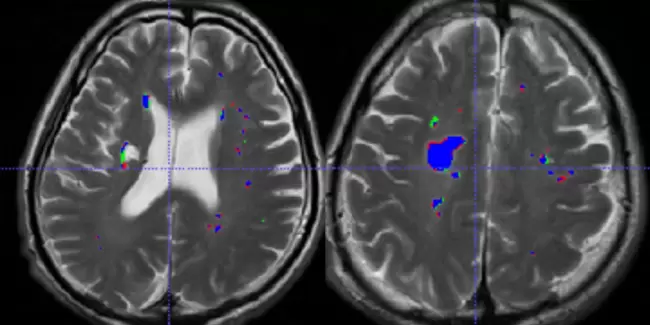

在医疗服务方面,宁波移动联合联仁健康医疗大数据科技股份有限公司全国率先推进医学影像AI服务应用平台建设,提供多模态、多厂家、多种类的智算适配加工,高效辅助医疗影像诊断,缩短医生阅片时间66%,准确率从80%提升至95%,目前已有效赋能属地11家基层医疗机构。在智慧党建方面,宁波移动与宁波市委党校打造全省首个党政教育行业数字人直播案例,通过AI数字人技术为党校老师量身打造独特的数字人形象和音色,以智能化辅助教学,极大提升了党课教学的效率和生动性。在反诈防骗领域,AI+谛听网络反欺诈平台,基于移动实时数据流量,提供面向公共安全领域的网络反欺诈防治SaaS级服务,通过态势感知、预警触达、以案查案及数据核验挖掘等功能实现网络反欺诈的闭环管理,累计开展AI智能语音外呼超3万次、下发短信预警超4万条,拦截诈骗类网址超22万个。